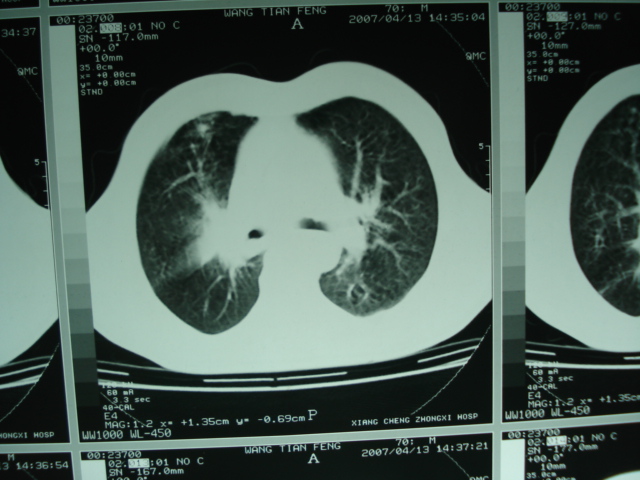

以下是引用狙击手在2007-4-18 20:17:00的发言:[br]原:2007/1/22号ct片:右肺上叶可见片状、云雾状高密度影,右肺上叶后段可见三角形高密度影,尖端指向肺门,右肺上叶后段支气管壁不规则增厚,管腔不规则增厚,纵隔未见肿大淋巴结.[br] 今ct:右肺上叶片状影增大,右肺上叶后段不张及右肺上叶后段支气管壁不规则增厚未见变化,右肺下叶背段支气管壁不规则增厚.[br] 如果考虑肺结核,但从临床证据看竟然没有一项支持肺结核,不知患者是否已经过正规抗结核治疗。没有的话,3个月了前后片看起来变化不大,似乎有不太符合肿瘤征象,不知患者是否抗炎治疗过,下叶支气管增粗还是要高度警惕,同意楼主意见,将常规病理,生化检查再做一遍。[br]

以下是引用狙击手在2007-4-18 20:17:00的发言:[br]原:2007/1/22号ct片:右肺上叶可见片状、云雾状高密度影,右肺上叶后段可见三角形高密度影,尖端指向肺门,右肺上叶后段支气管壁不规则增厚,管腔不规则增厚,纵隔未见肿大淋巴结.[br] 今ct:右肺上叶片状影增大,右肺上叶后段不张及右肺上叶后段支气管壁不规则增厚未见变化,右肺下叶背段支气管壁不规则增厚.[br] 如果考虑肺结核,但从临床证据看竟然没有一项支持肺结核,不知患者是否已经过正规抗结核治疗。没有的话,3个月了前后片看起来变化不大,似乎有不太符合肿瘤征象,不知患者是否抗炎治疗过,下叶支气管增粗还是要高度警惕,同意楼主意见,将常规病理,生化检查在做一遍。[br]